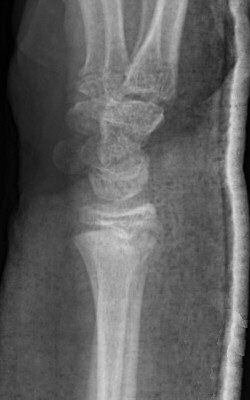

Dorsalbockad distal radiusfyseolys Salter-Harris typ 2 före och efter reposition